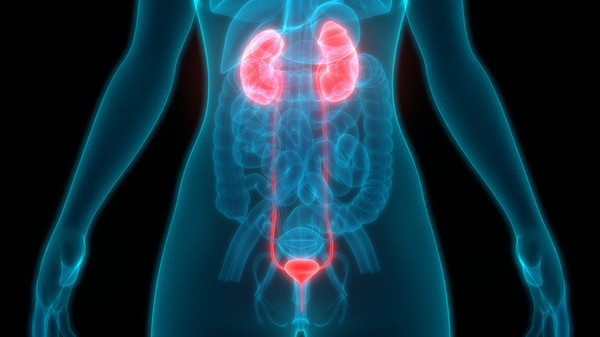

전립선암 초기증상 9. 혈뇨

혈뇨는 소변에 피가 섞여 나오는 증상으로, 상식적으로 신장이나 방광에 문제가 있다는 신호일 수 있으기 때문에 미리 체크를 받아보는 것이 좋아요. 전립선암도 혈뇨의 흔한 원인인데요. 전립선의 암세포는 전립선으로 출혈을 일으켜 혈뇨를 일으킬 수 있지만, 혈뇨는 전립선암의 흔한 증상일 뿐 아니라 요로감염이나 전립선의 거시적 문제와 같은 다른 일시적인 원인으로도 확인될 수 있어요.